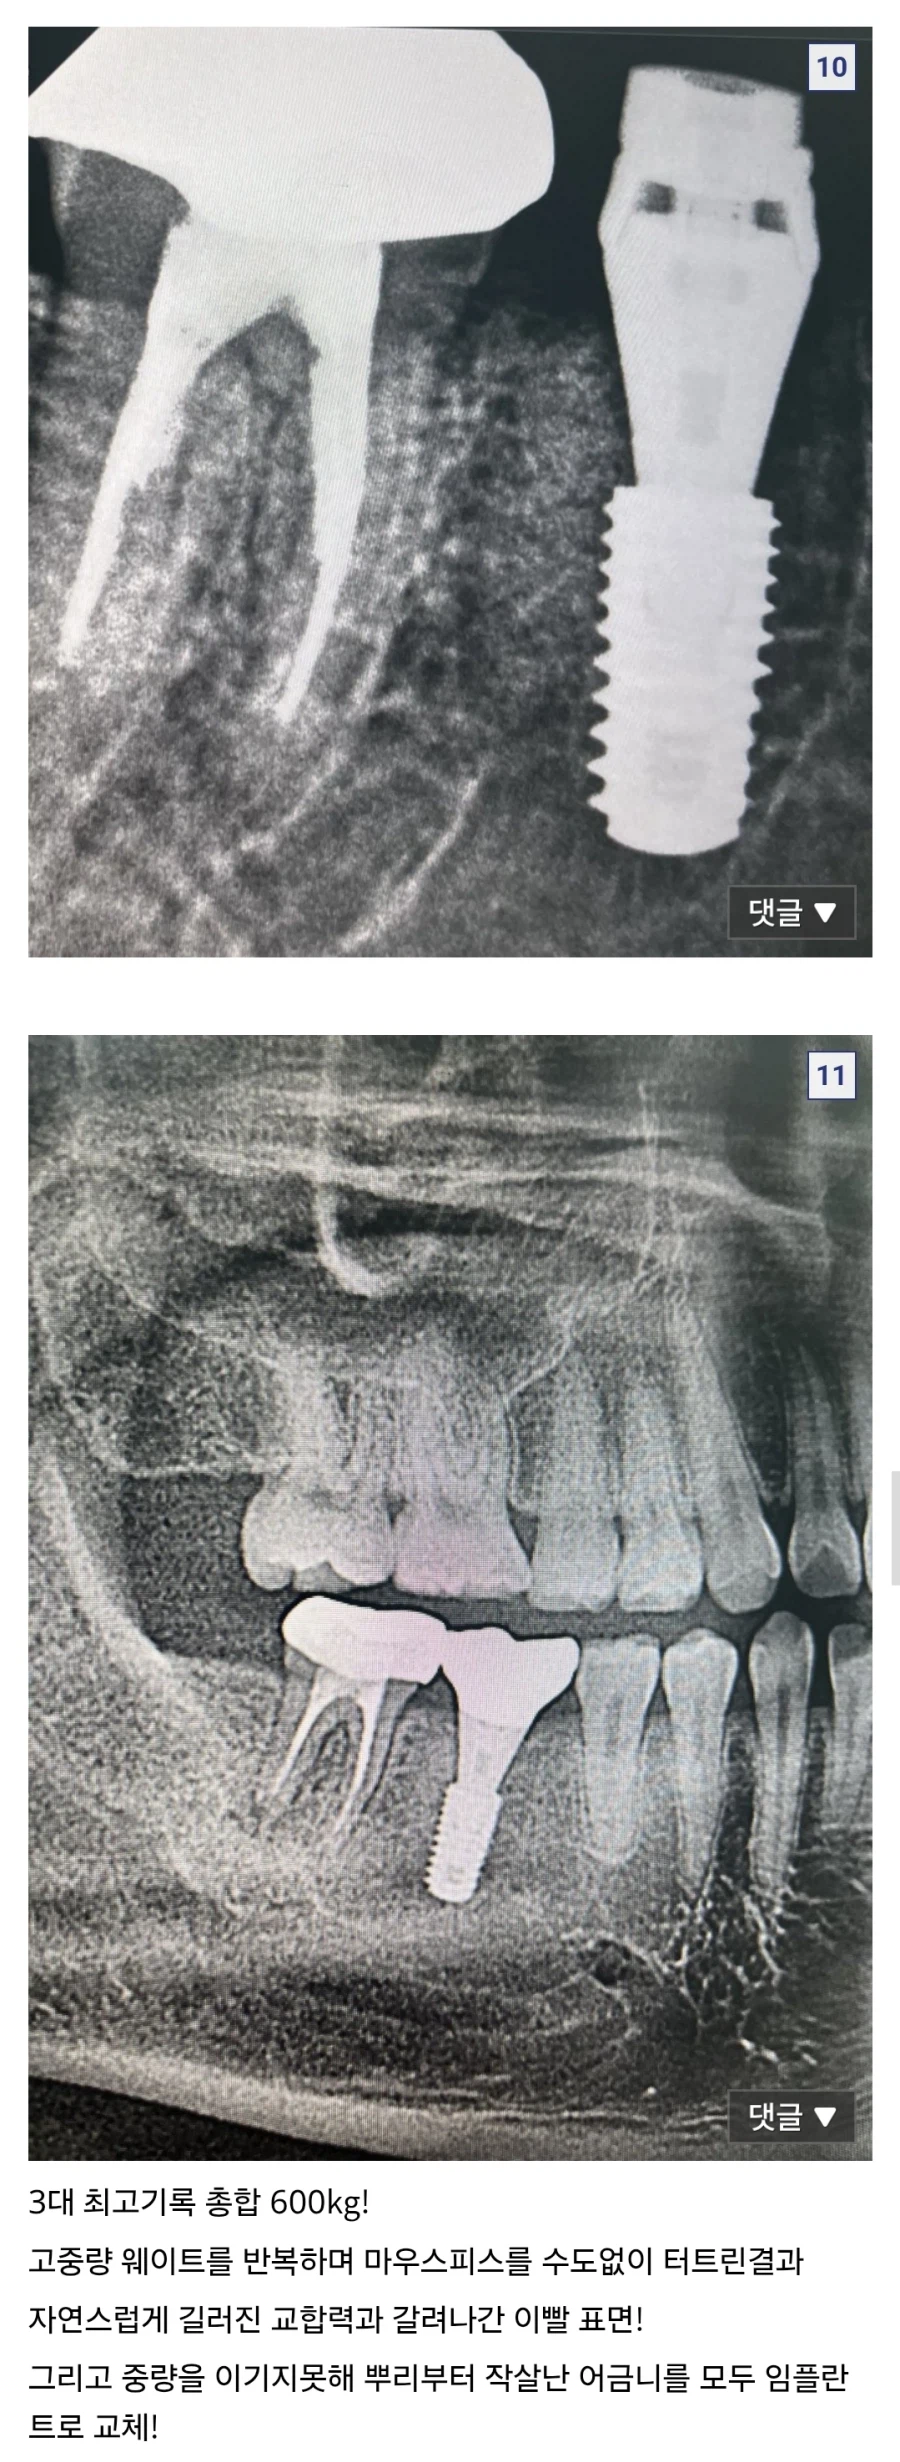

바키)바붕아... 너는 너 무 강 해 졌 다 Anonymous | 2026.03.21 09:41 | 조회 6 https://qquing.net/bbs/board.php?bo_table=humor&wr_id=1861390 주소 복사 이전글 다음글 랜덤 만화 목록 본문 추천 0 비추천 0